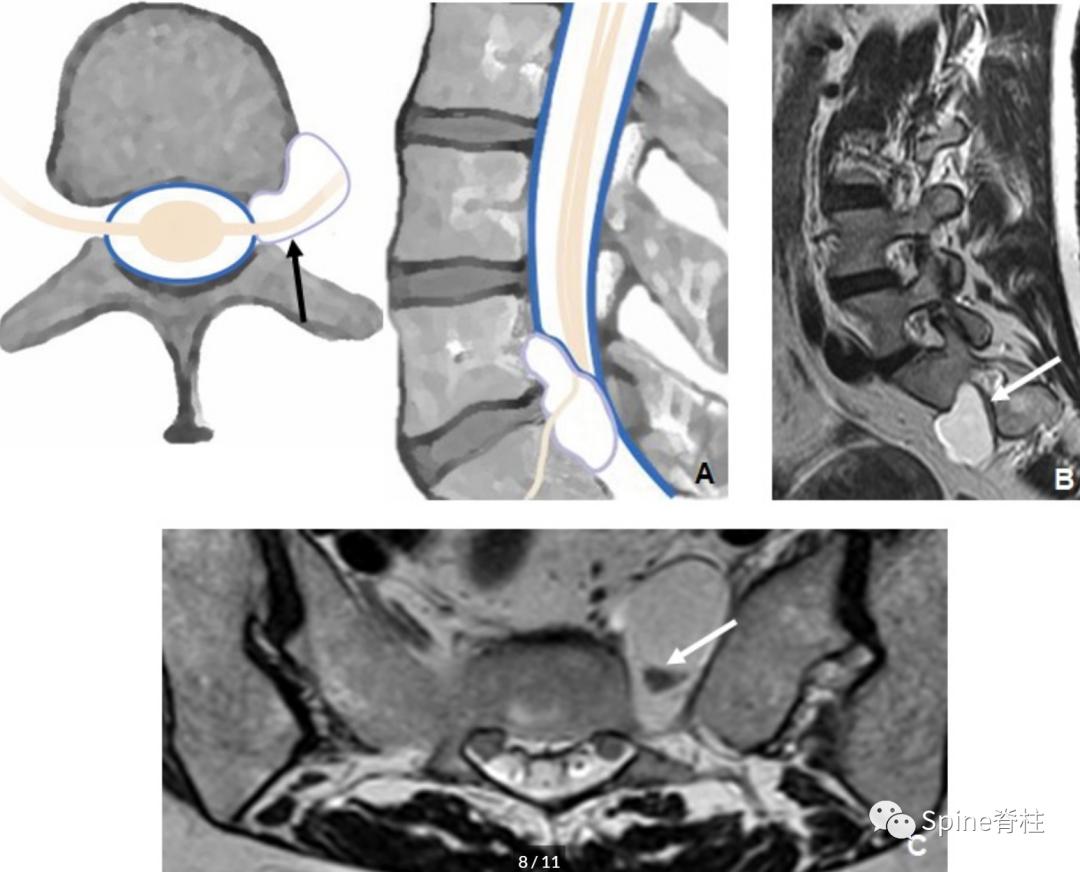

1. 滑膜囊肿 (synovial cysts):具有滑膜内皮细胞,与小关节腔连通并含有滑液。通常与相邻的小关节病变有关,且主要发生在腰段。在MRI上,滑膜囊肿边界清楚、光滑, 位于硬膜外且邻近小关节 。在T1和T2加权像上,囊肿内的蛋白质成份可显示出比周围脑脊液更明显的信号强度(下图)。囊壁可能会钙化,在T1和T2加权图像中呈现低信号,增强后囊壁可见强化。

一名55岁患者腰椎MRI提示L5/S1滑膜囊肿(箭头),右侧S1神经根明显受压。囊肿邻近肥大的小关节突

2. 假性囊肿 (pseudocysts): 假性囊肿或神经节囊肿可能是小关节、黄韧带或后纵韧带囊肿,具体取决于其解剖起源。其与真性囊肿具有共同的症状和影像学特征,但不与小关节腔直接相通。这些囊肿被认为是由脊柱活动中韧带的退变引起(下图)。

一名62岁患者腰椎MRI提示L4-L5平面的椎管内硬膜外黄韧带囊肿(蓝色箭头),绿色箭头为邻近肥厚的黄韧带